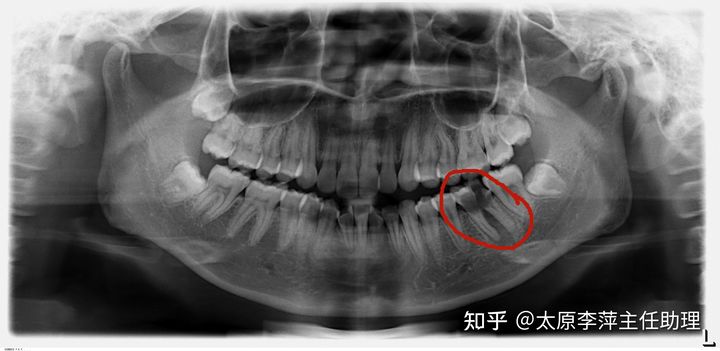

检查:牙列轻度拥挤,上下颌均前突。口内左下磨牙残冠。

另外,该患者左下磨牙残冠,不能保留。而她左下正好有一颗智齿,影像显示牙齿发育较好。所以我们制定了一个比较费时费力的拔牙治疗方案——左下只需要拔除磨牙残冠,其他象限常规拔除第一双尖牙。这个拔牙设计,左下拔除磨牙,对于拔牙位越靠后,越不利于前牙前突的解决。后牙的近移,也需要对磨牙牙根平行移动得更好控制。